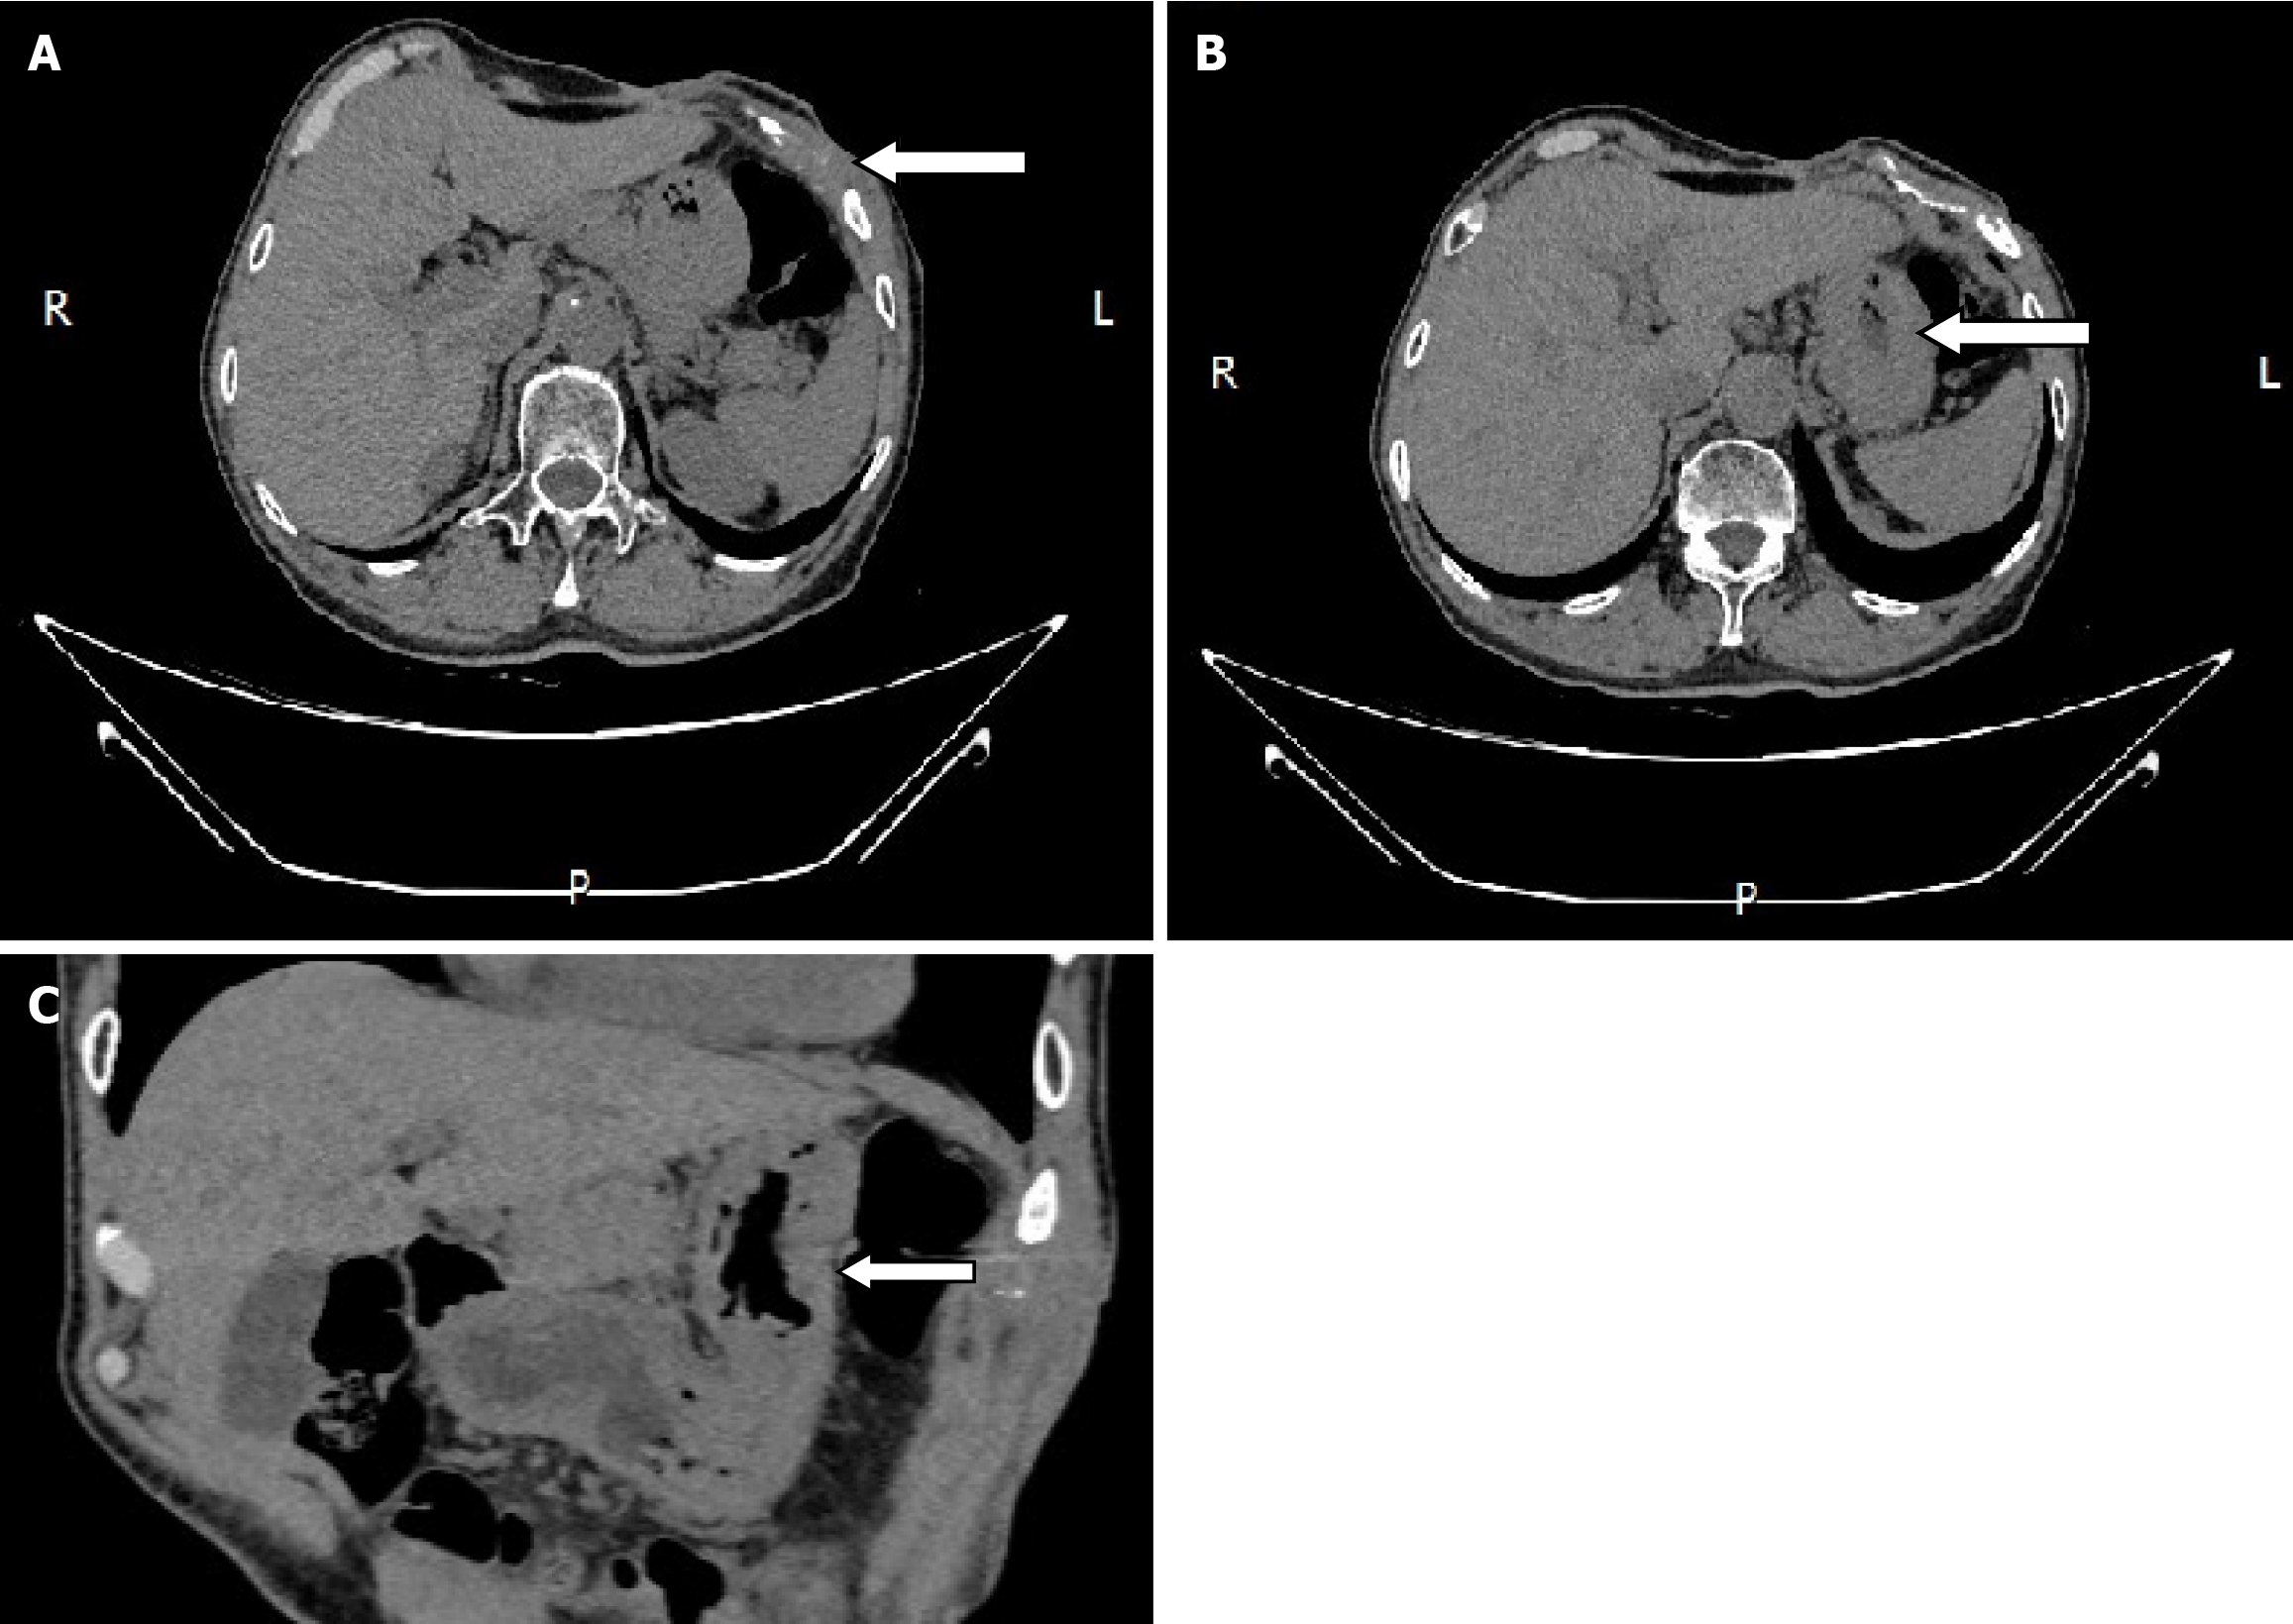

During the postoperative fasting period, we consulted with a nutritionist again. The energy and nitrogen sources were supplied according to the patient's disease status until he returned to a roughly normal diet and then changed to oral enteral nutrition. Drainage tubes of smaller diameter were placed successively and then removed. Reexamination by abdominal CT confirmed that the thoracoabdominal wall swelling had improved (Figure 5), gastric endoscopy verified gastric ulcer improvement and the gastric fistula was not observed at this time (Figure 6). The patient’s clinical symptoms, especially pain, were alleviated. Pathological examination of the sinus showed fibrous and inflammatory granulation tissue with a giant cell reaction. His condition improved and he was again discharged on June 17, 2020.

Although the patient was discharged with mild pain on September 14, 2020, we were confident that he would have a complete recovery and it was proved by reexamination 3 months later (Figure 7). The patient was then followed up for more than 4 years without recurrence. Time-line about diagnosis and treatment of the patient was shown on Figure 8.